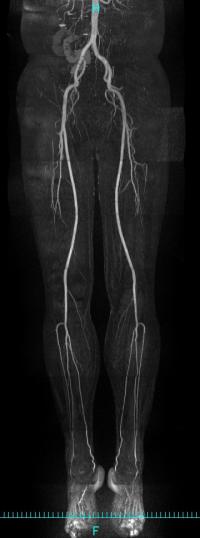

筒状の磁石の中にある身体に電波を当てると少しだけ電波が返ってきます。それを集め画像化する技術です。あらゆる断面が容易に観察でき、いろいろなコントラストの情報が得られる、解剖学的、質的診断にきわめて有用な検査です。造影剤を使用せず血管の様子を観察できる利点もあります。

下肢血管